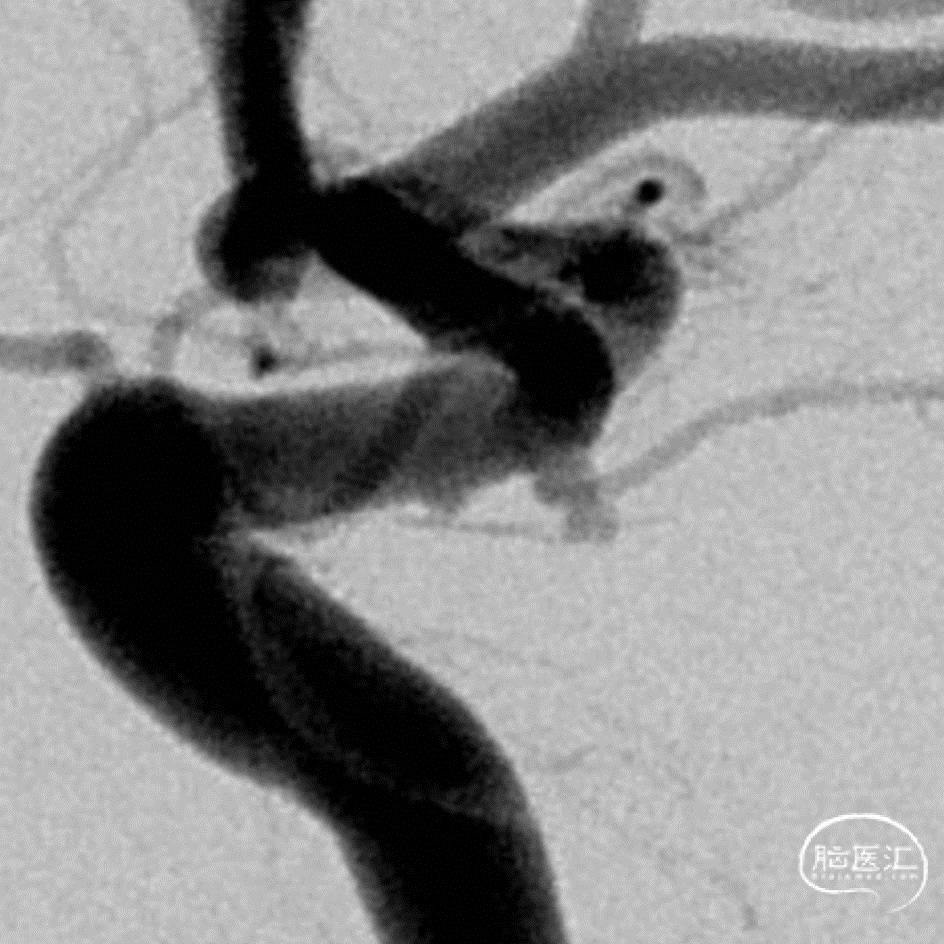

正位造影

侧位造影

DSA:数值测量

工作角度造影

数值测量